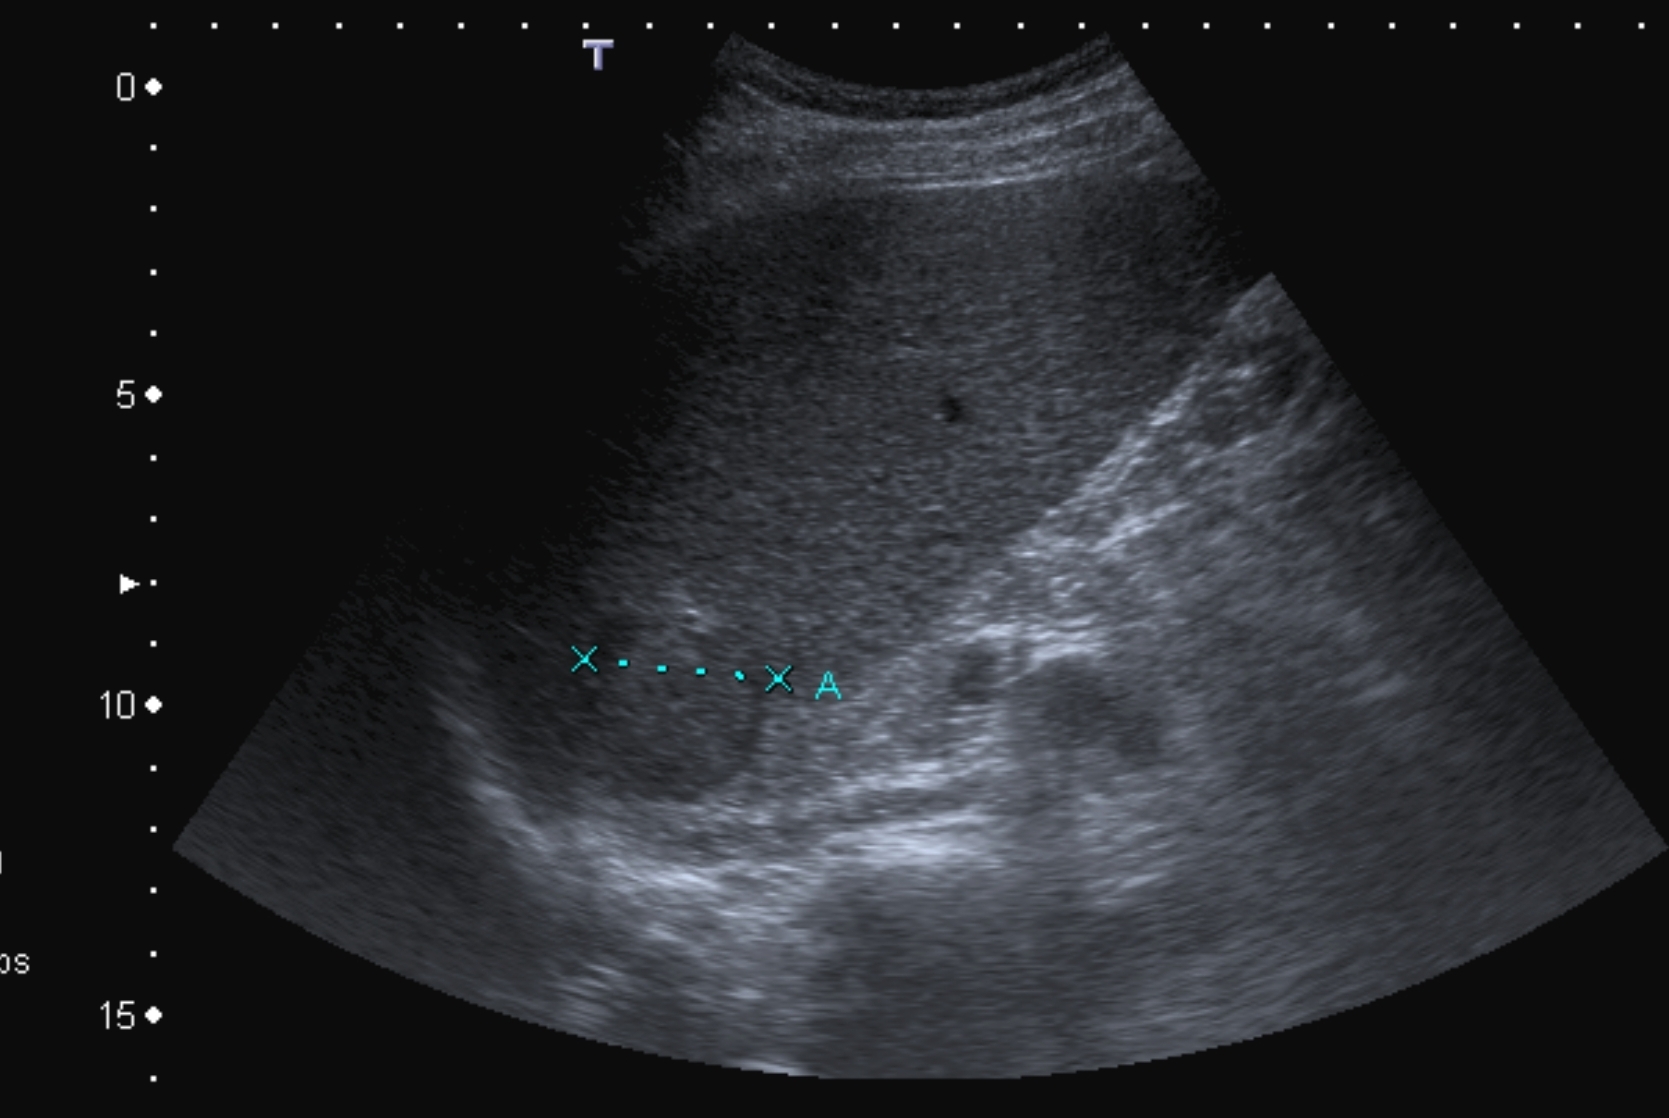

Concerning the HCC, the knowledge of history is very important for the decision and usually the oncoteams consider the performance of an imaging modality guided biopsy basically important for the further therapeutic decisions (because of the hystological validation rather core biopsy should be performed! (Figure 26, 27, 28).

Figure 26: HCC, verified with FNAB, US